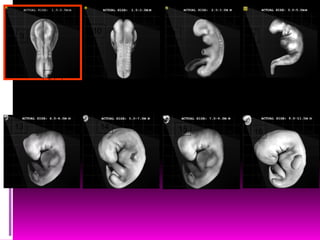

PERIODO ORGANOGENETICO

DE LA CUARTA A LA

OCTAVA SEMANA

ORGANOGÉNESIS

 Es la mayor parte del

período embrionario

 Ya están establecidas

todas las estructuras

internas y externas.

FASES DEL

DESARROLLO

EMBRIONARIO:

 Crecimiento (aumento

de tamaño)

 Morfogénesis

(desarrollo de la forma)

 Diferenciación

(maduración de

procesos fisiológicos)

PLEGAMIENTOS DEL EMBRIÓN

Cuarta semana

 Mide 2 ª 3.5mm de largo.

 Es casi recto

 Tiene 4 a 12 somitas

 Se forma el tubo neural

entre somitas opuestas.

Quinta semana

 QUINTA SEMANA

 Mayor crecimiento de la cabeza

 Rudimentos de los riñones

Sexta semana

SEXTA SEMANA

 Desarrollo de los codos y placas de las manos,

rayos digitales (futuros dedos), ya mueve el

tronco y los miembros.

 Conducto auditivo y pabellón auricular

 Cabeza más grande el relación con el tronco.

 Muestran respuesta refleja al tacto.